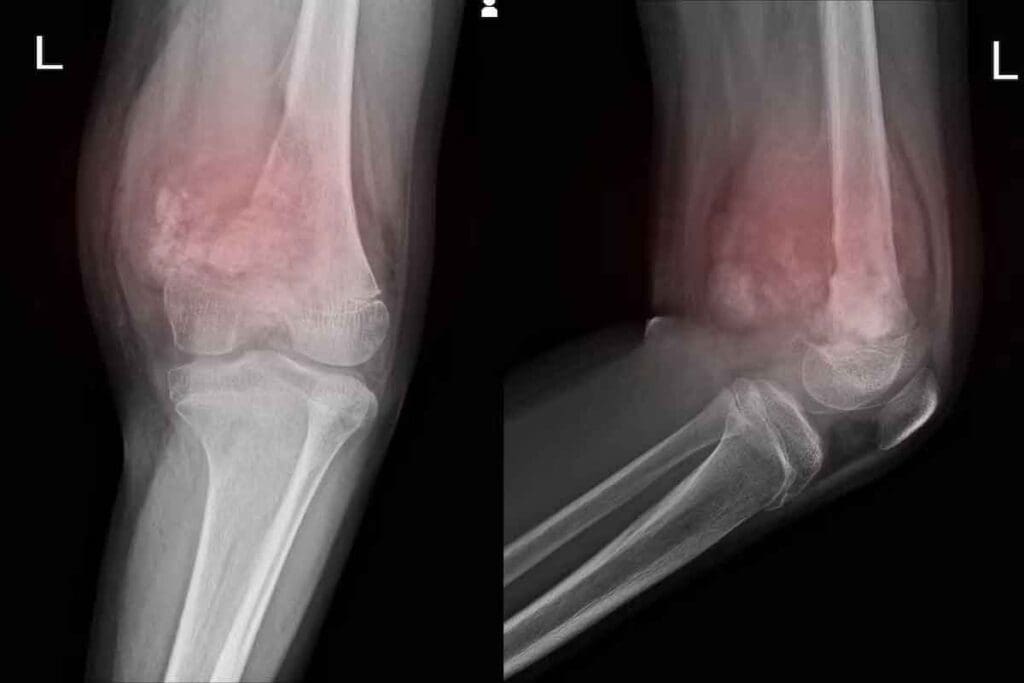

Imaging Modalities and Their Role

Imaging studies are key in diagnosing Ewing Sarcoma. MRI and CT scans help see how big the tumor is and if it has spread. MRI is great for checking soft tissue and how the tumor affects nearby areas.

How is Ewing Sarcoma diagnosed?

Diagnosis uses imaging like X-rays, MRI, and CT scans. A biopsy examines tissue samples. Molecular tests look for genetic changes. Histopathology confirms the diagnosis.